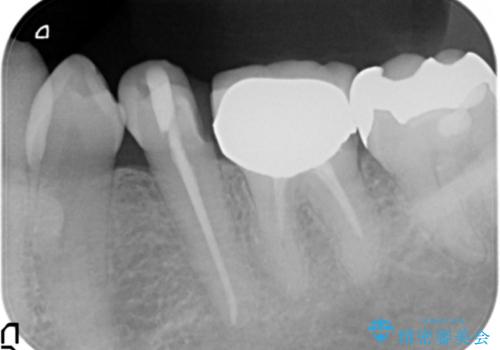

- 虫歯治療、老朽化した銀歯や詰め物 コンポジットレジンのやりかえを希望され来院されました。

クラウンやレジン下に再発していた虫歯を丁寧に除去したのち、歯ぐきの腫れが改善が見られないため歯周外科を行い歯ぐきの状態を整えたのちにジルコニアクラウンを製作していきます。

クラウン治療を行う場合歯ぐきの腫れが、クラウン製作の精密さにおいて問題点となることがあります。

このような場合、歯周外科を行うことでクラウン周囲の歯茎の状態を整備し精度に優れる治療を行うことができます。